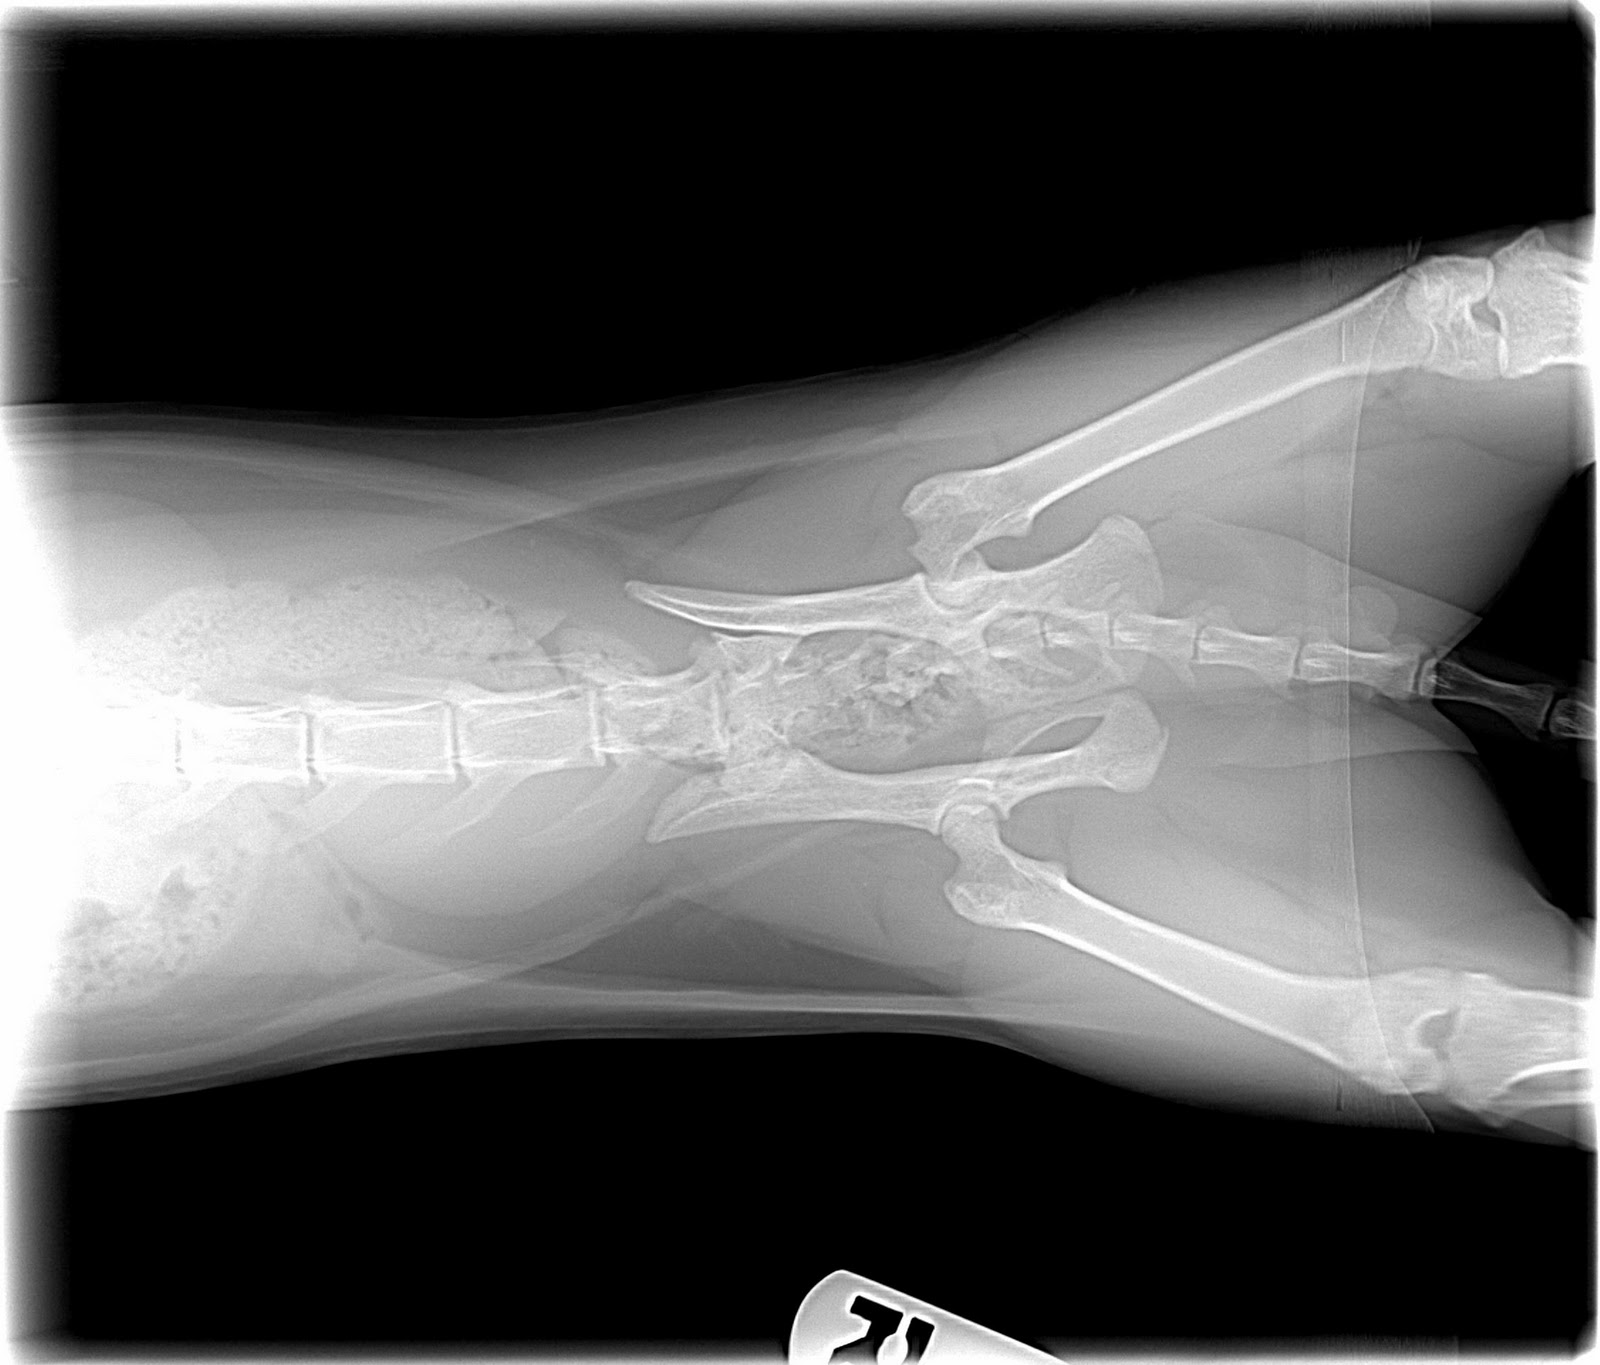

From journals.sagepub.com

Treatment of pelvic fractures in cats with patellar fracture and dental Can A Cat Survive A Broken Hip Hip dislocation, from hip dysplasia or from injury, along with a luxating patella (sliding knee cap) are among the most common. A dislocated hip or fractured bone can be. In pets, fractures are usually due to something traumatic, like a fall, an animal attack, or being hit by a car. If you suspect that your cat has a broken hip,. Can A Cat Survive A Broken Hip.